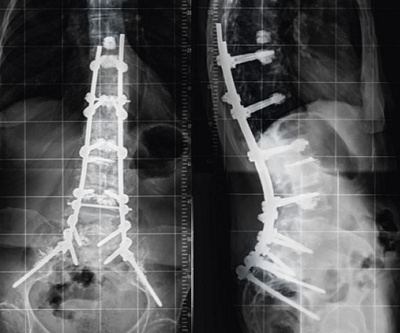

Wenn alle diese Massnahmen nicht ausreichen, besteht die Möglichkeit einer Operation. In der Regel sind grössere Operationen notwendig, um den Rücken in ein gutes Gleichgewicht zu bringen. Versteifungen des Rückens sind dabei meist nicht zu vermeiden, so dass eine Einschränkung der Beweglichkeit die Folge ist (Abb. 2 und 3).

Abb. 2

Röntgenbilder von vorn (links) und von der Seite, 78-jährige Patientin mit schwerer Fehlhaltung vor der Operation

Abb. 3

Röntgenbilder derselben Patientin nach der Operation